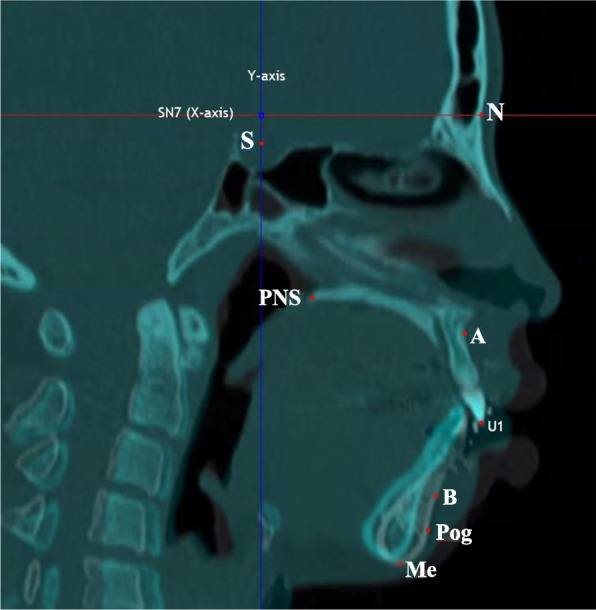

Methods: The study included 16 patients (6 with Class II malocclusion, 10 with Class III malocclusion) who underwent bilateral sagittal split ramus osteotomy at Chonnam National University Hospital. Cone-beam CT data were collected at three specific time points: before surgery, immediately after surgery, and approximately 6 months post-surgery. Mandibular movement was measured using InVivoDental 5.4.6. ITK-SNAP 3.8.0 was used to assessed condylar volume changes post-surgery. Condyle positions were evaluated in four parts with RadiAnt DICOM Viewer 4.6.9. Statistical analyses were performed using the SPSS version 23.

Results: Considering both Class II and III malocclusion, a 2.91% volume reduction was noted immediately and at 6 months after surgery. Both Class II and III cases demonstrated a decrease in superior joint space by -0.59 mm and medial joint space by -1.09 mm. No significant correlation was found between this process and condylar volume change.